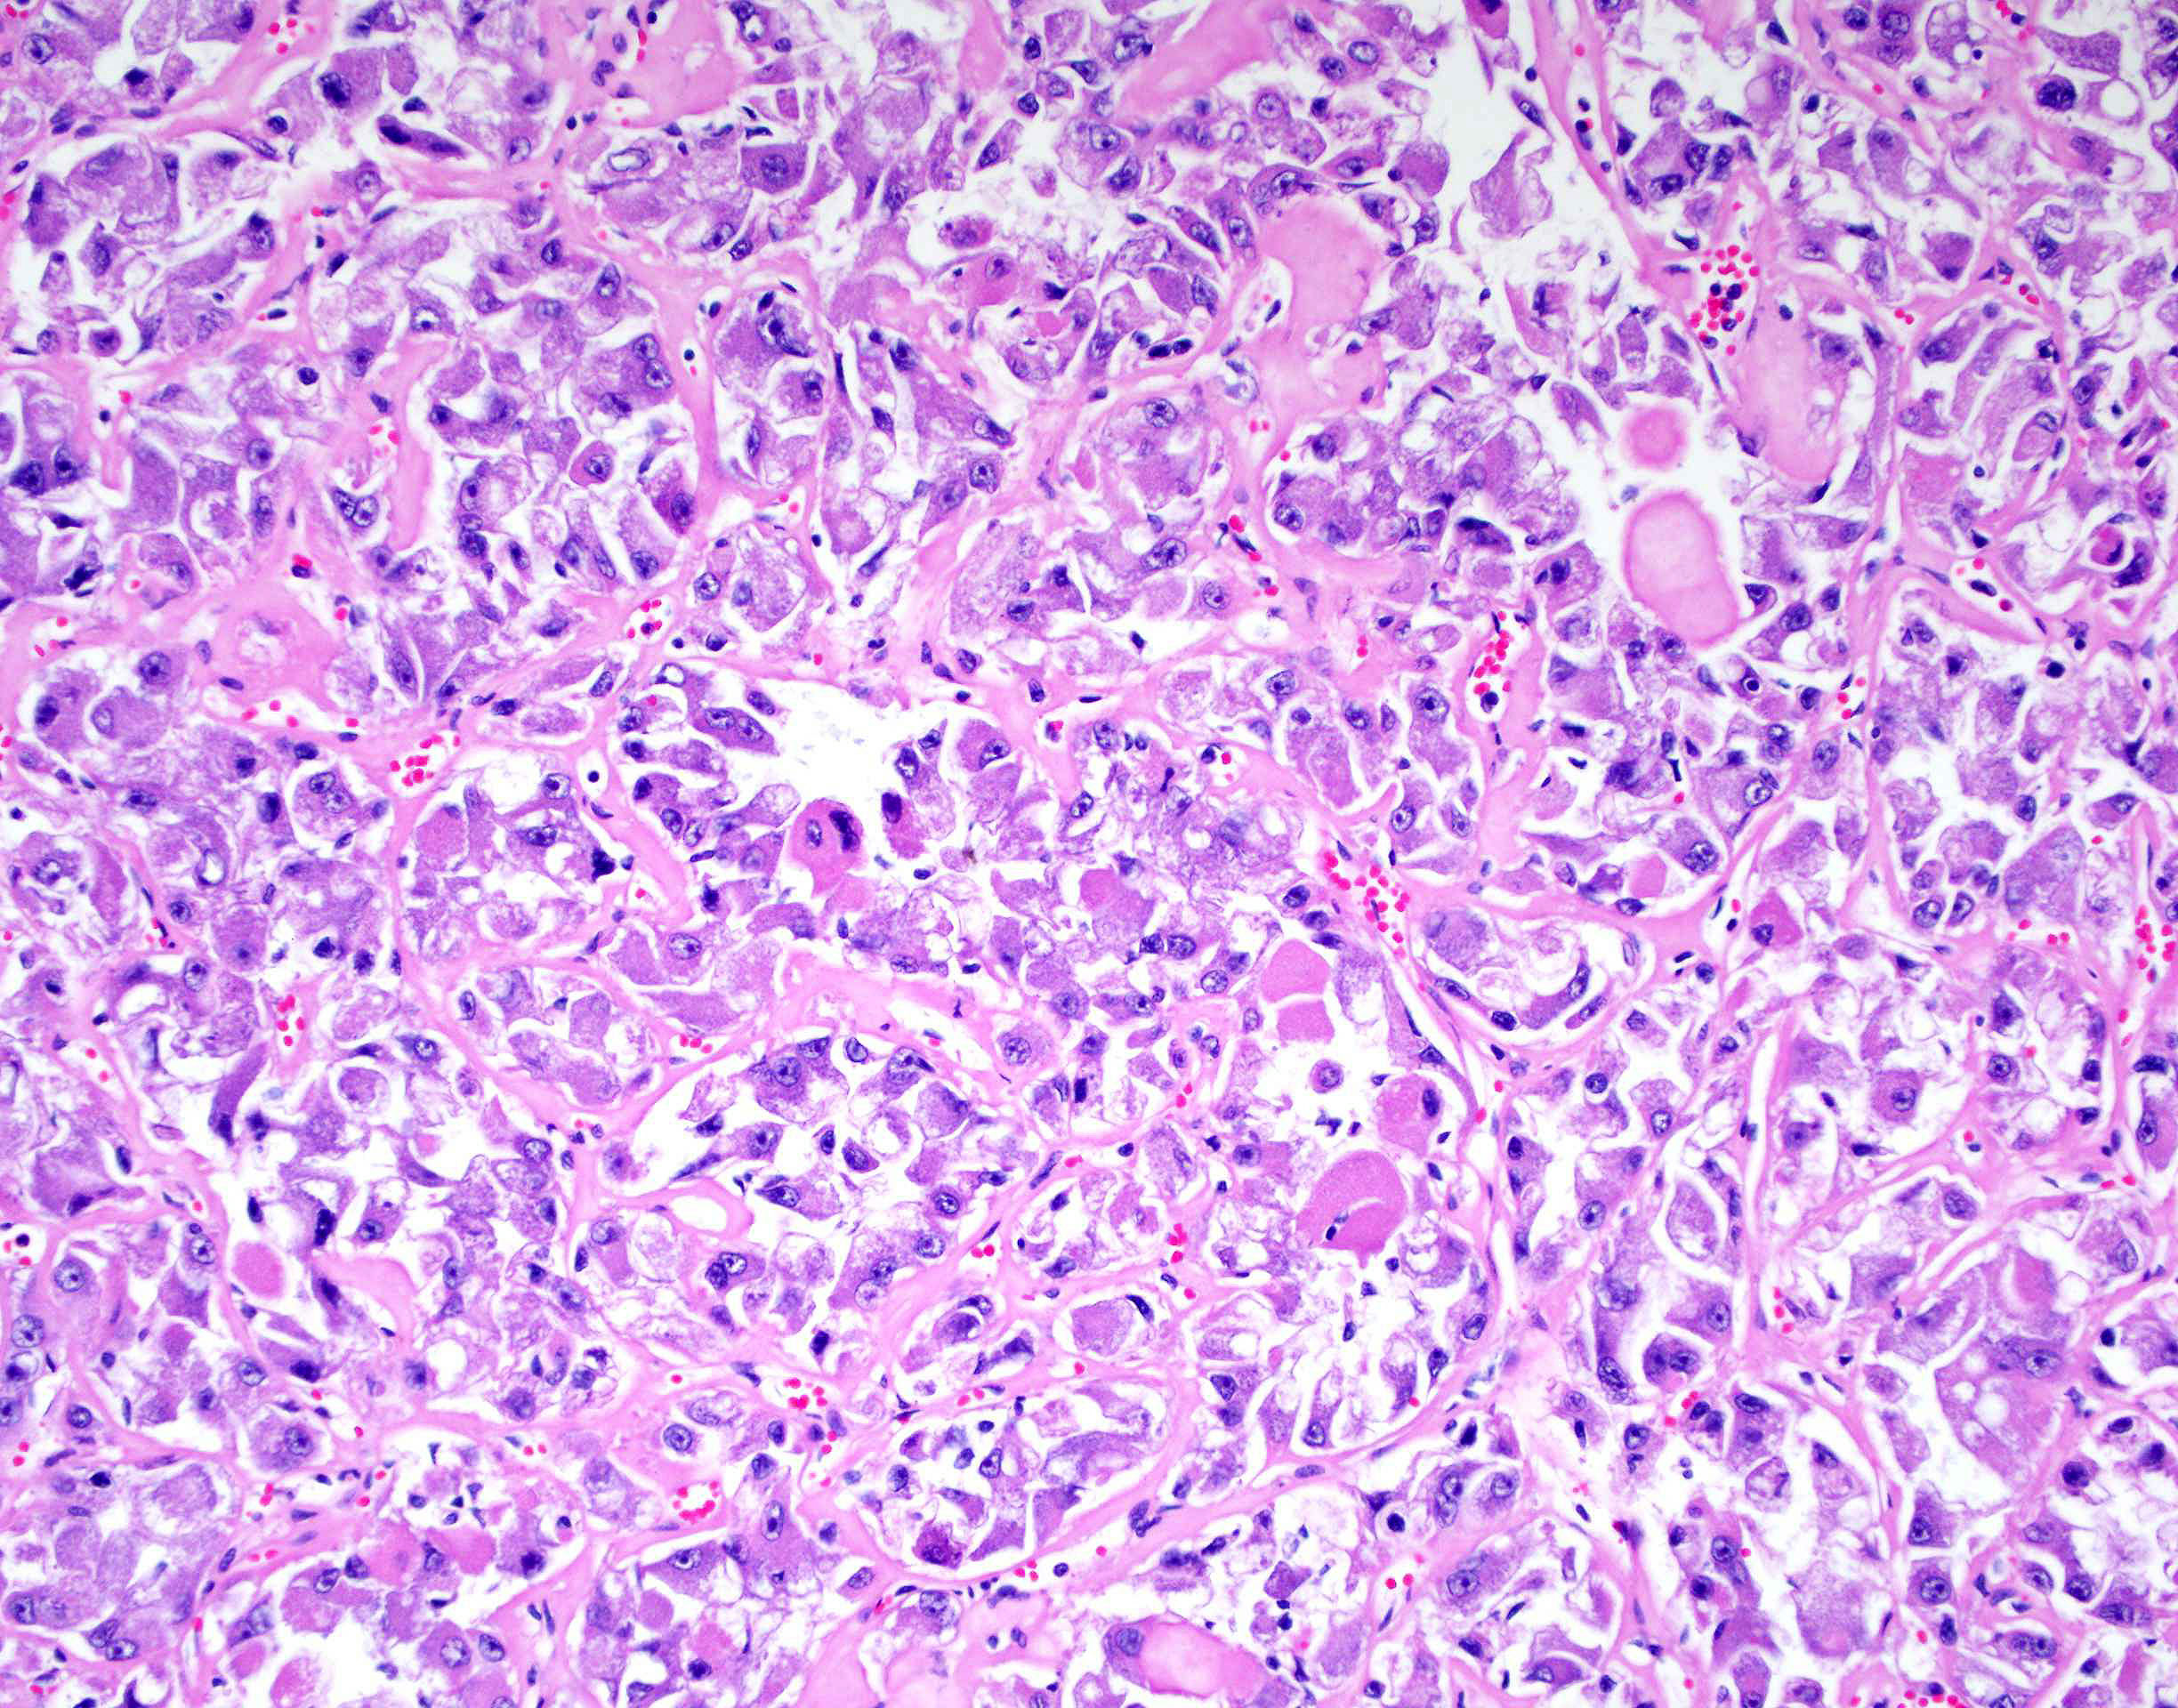

Renal tumor grading

Case ID: 419